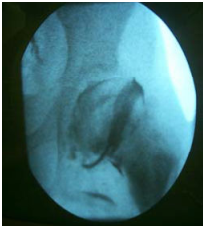

A figura a seguir apresenta o exame de imagem do quadril de um paciente.

Diante do exposto, é correto afirmar que trata-se de uma